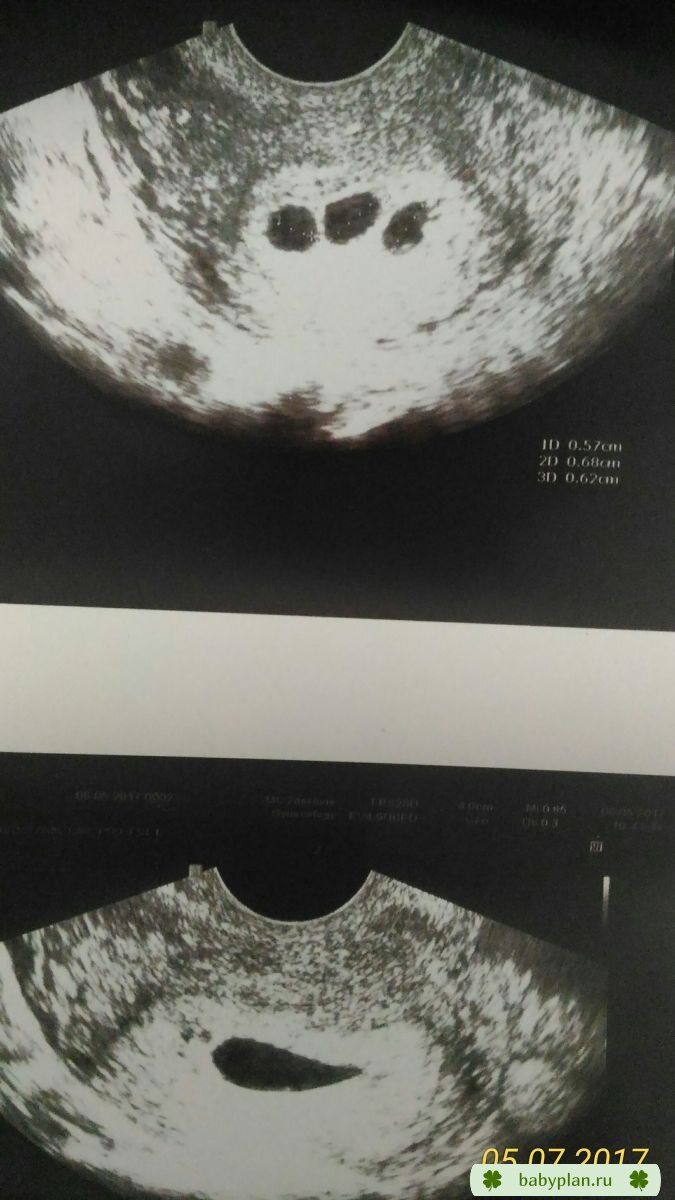

Медицина и диагностика: Инвазивный пузырный занос на УЗИ

Раздел: Альбом идей